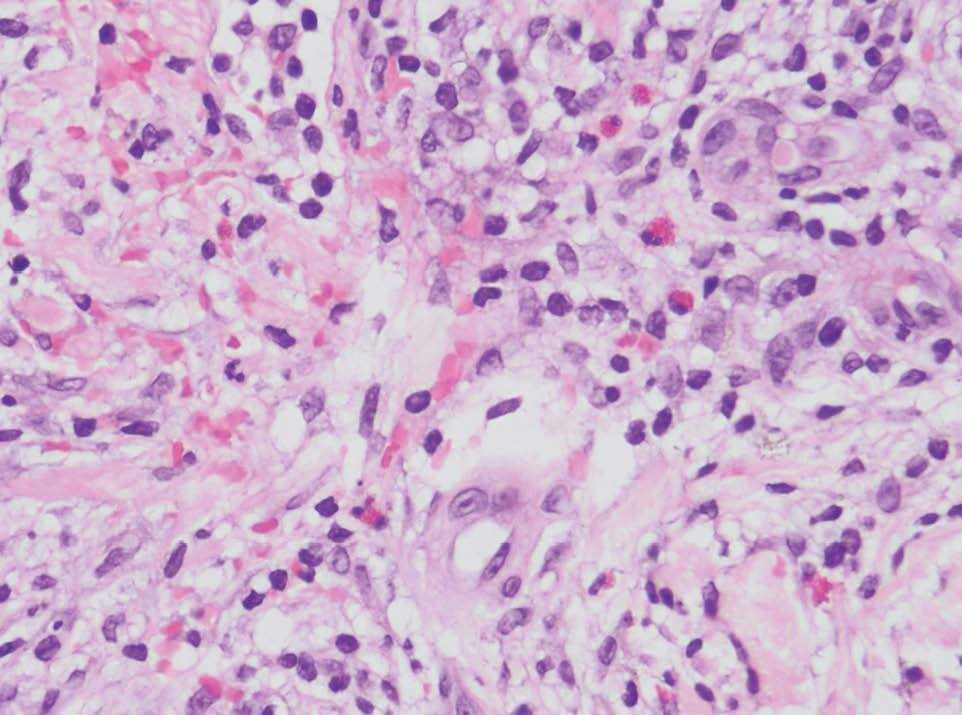

En la analítica destacaba la presencia de 36.800 leucocitos/mm 3 con 81 % de linfocitos; la bioquímica y la coagulación eran normales. Se realizó una biopsia cutánea de una ampolla (fig. 3) y de una pápula edematosa (fig. 4).

Fig. 3.--Ampolla subepidérmica que contiene fibrina, células mononucleares y múltiples eosinófilos. (Hematoxilina-eosina, x10.)

En la biopsia de la lesión ampollosa se aprecia una ampolla subepidérmica, cuyo techo está constituido por un epitelio parcialmente necrótico con reepitelización y el suelo por las papilas dérmicas. La ampolla contiene fibrina, células mononucleadas y múltiples eosinófilos (fig. 3). En la pápula edematosa existe en la epidermis un intenso edema inter e intracelular, que induce la formación de vesículas basales y ruptura de la membrana basal. En ambas biopsias vemos en toda la dermis reacción inflamatoria perivascular e intersticial de células mononucleadas con abundantes eosinófilos, intensa ectasia capilar y edema (fig. 4). La inmunofluorescencia directa sobre piel perilesional de una ampolla fue negativa.